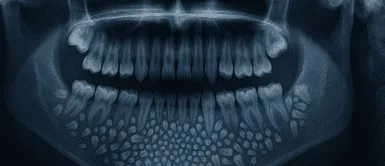

Los estudios radiográficos y las tomografías mostraron una masa de cerca de 200 gramos en el interior de la mandíbula. El Dr. Senthilnathan, jefe del Departamento de Cirugía Oral y Maxilofacial, determinó que se trataba de un “odontoma compuesto”, un tipo de tumor benigno relacionado directamente con la formación dental.

El resultado sorprendió incluso a los profesionales con mayor experiencia. De acuerdo con Science Alert, el saco contenía 526 piezas dentales en miniatura que variaban entre 0,1 milímetros y 15 milímetros de longitud. El proceso de clasificación y conteo de cada diente tomó cinco horas adicionales de trabajo de laboratorio.

La Dra. Pratibha Ramani, directora del área de Patología Oral y Maxilofacial, resaltó que todas las piezas extraídas poseían las características propias de un diente normal: corona, raíz y esmalte. “Incluso la pieza más pequeña tenía las características de un diente tradicional”, precisó la especialista, remarcando que no existen antecedentes con tal cantidad de dientes en registros médicos internacionales.